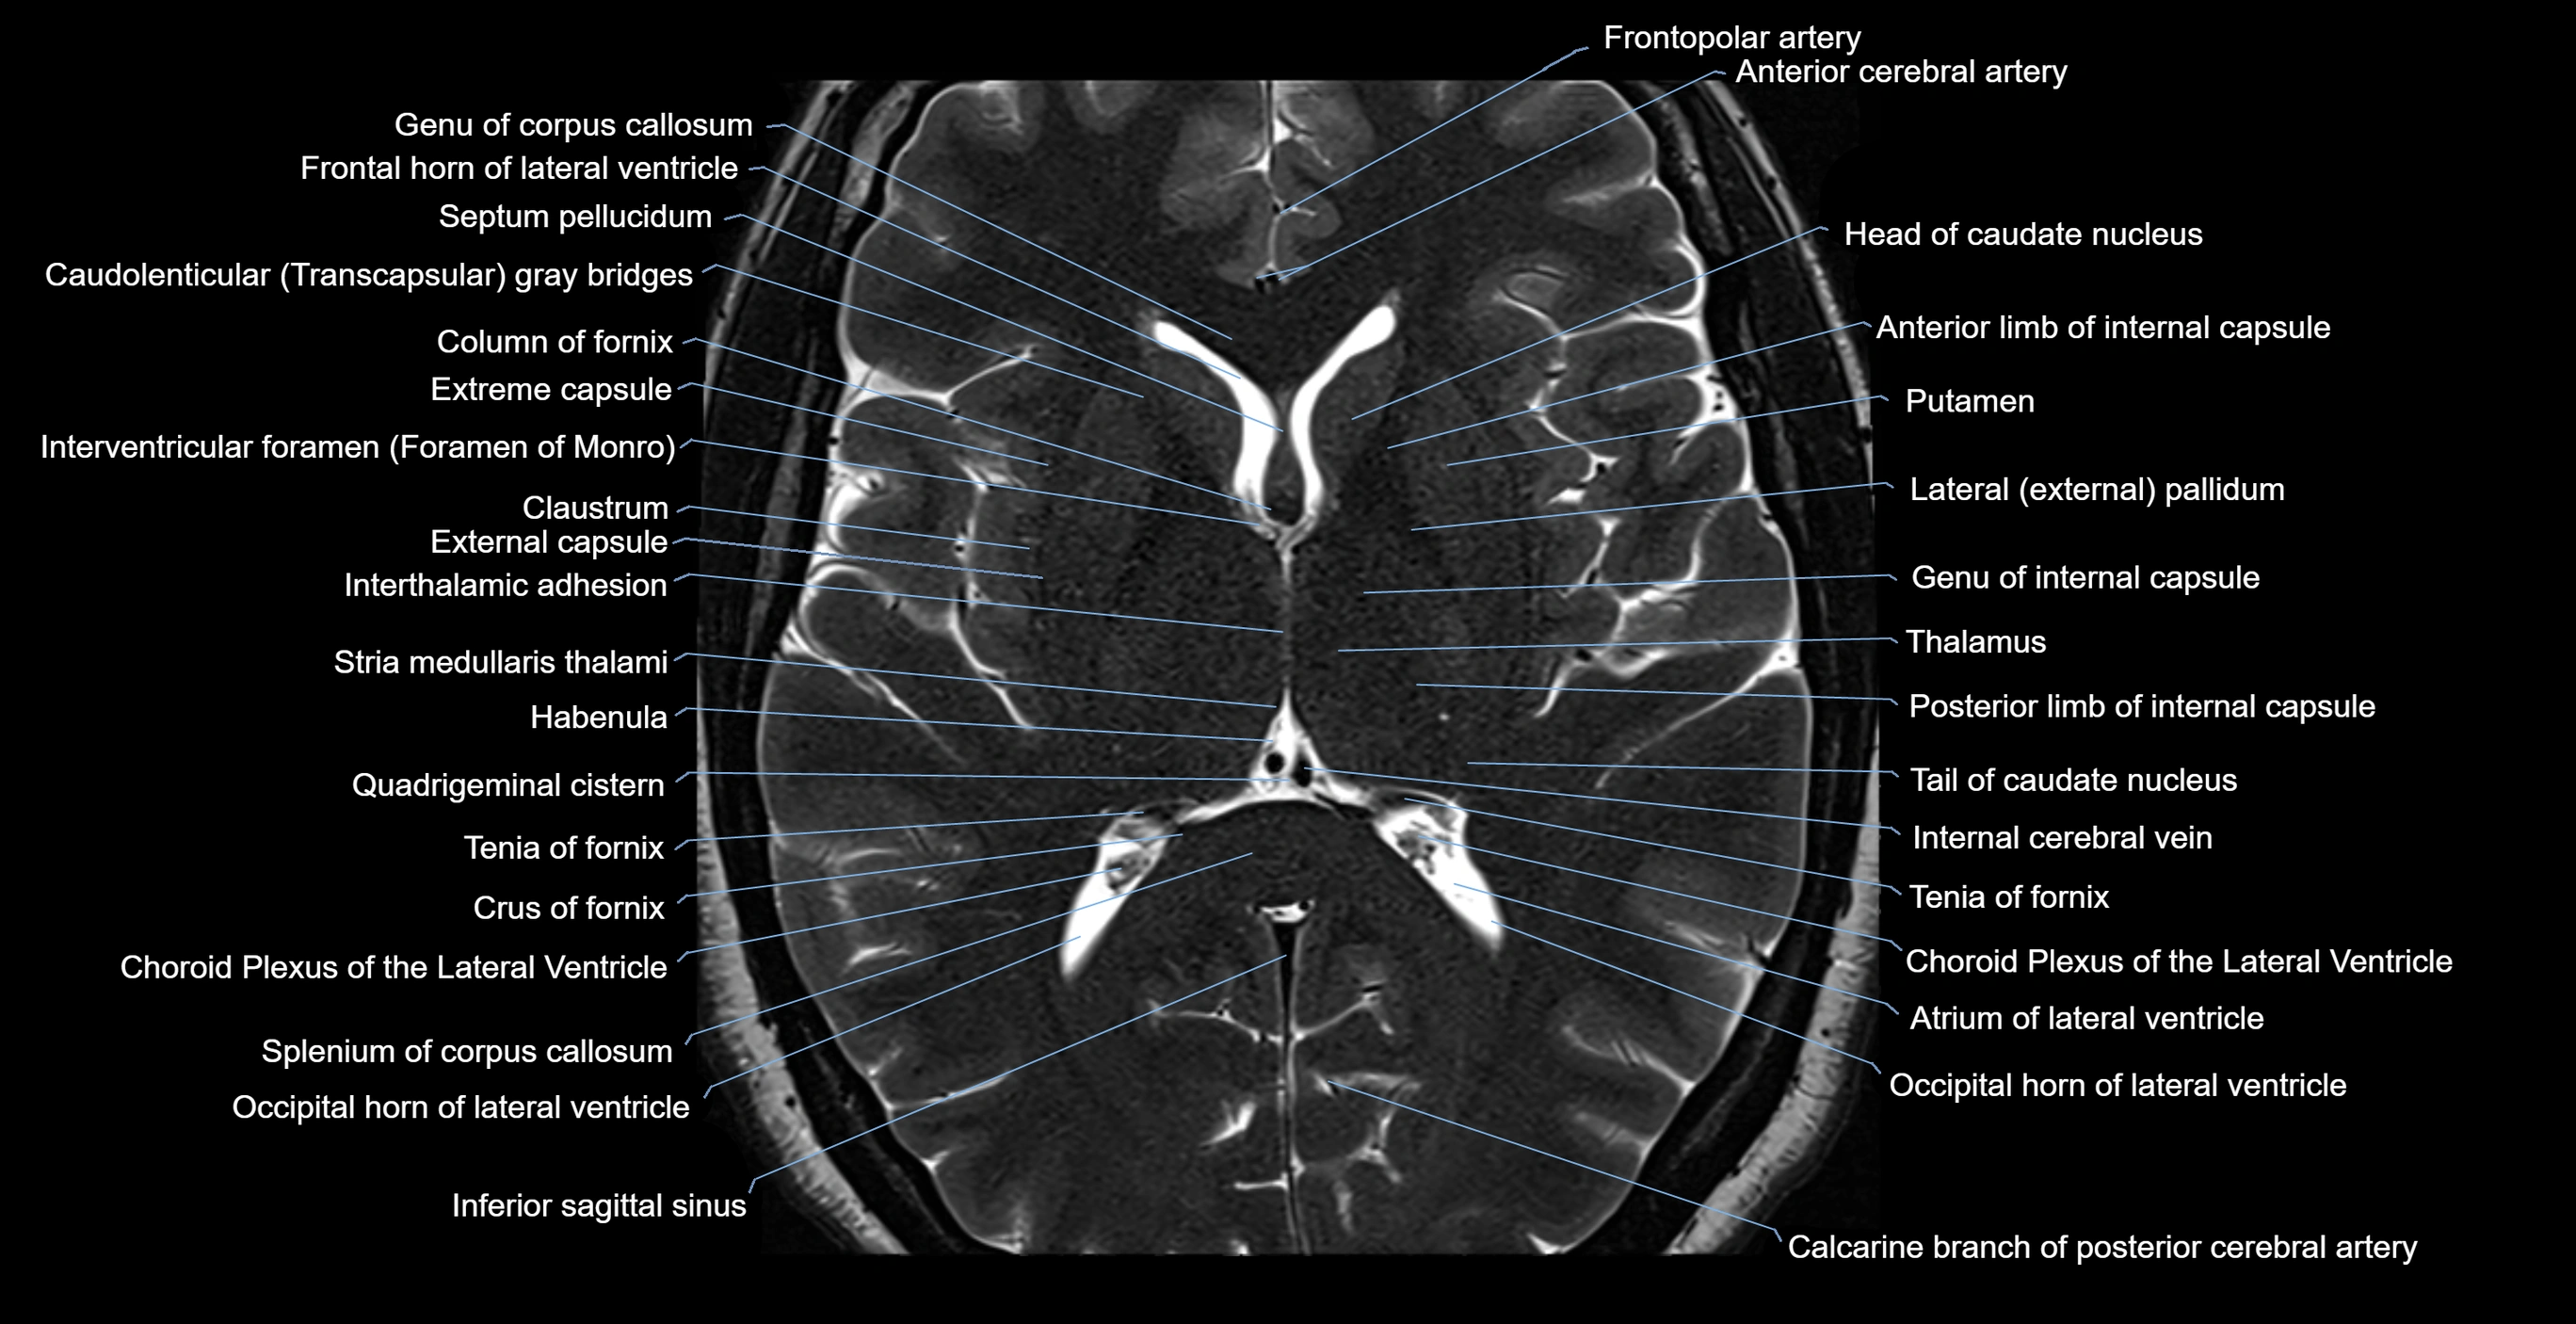

- Anterior limb of internal capsule

- Atrium of lateral ventricle

- Body of caudate nucleus

- Body of corpus callosum

- Body of lateral ventricle

- Calcarine branch of posterior cerebral artery

- Caudato-lenticular bridges

- Caudatolenticular gray bridges

- Claustrum

- Column of fornix

- Crus of fornix

- External capsule

- Extreme capsule

- Frontal horn of lateral ventricle

- Frontopolar artery

- Genu of corpus callosum

- Habenula

- Head of caudate nucleus

- Inferior sagittal sinus

- Internal cerebral vein

- Interthalamic adhesion

- Interventricular foramen

- Lateral pallidum

- Occipital horn of lateral ventricle

- Posterior limb of internal capsule

- Putamen

- Quadrigeminal cistern

- Rostrum of corpus callosum

- Splenium of corpus callosum

- Tail of caudate nucleus

- Tenia of fornix

- Thalamus

- Third ventricle

- genu of internal capsule